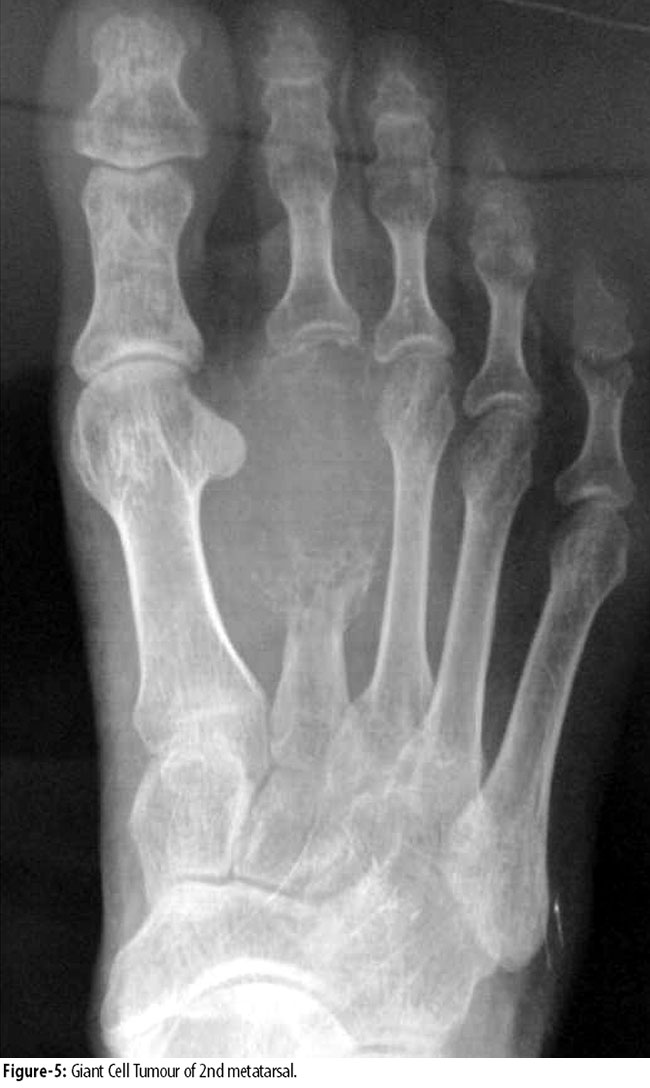

and 1(0.4%) in 2nd metatarsal were in stage3 (Figure 5 and 6),

and were treated by en-bloc resection and reconstruction with free fibular graft. Fibular graft was held with intramedullary K-wire. Rest of the tumours in all metatarsals were stage 2 and were treated by curettage and autologous cancellous bone grafting. In 2(0.8%) cases of phalanges, 1(0.4%) in proximal phalanx of big toe was treated by resection and fibular bone grafting and 1(0.4%) was treated by amputation of 3rd toe. There was 1(0.4%) recurrence in calcaneus and 1(0.4%) in 1st metatarsal, both of which were initially treated by curettage and bone grafting. Calcaneus recurrence was treated by below-knee amputation and 1st metatarsal recurrence by resection and iliac crest cortico cancellous bone graft.